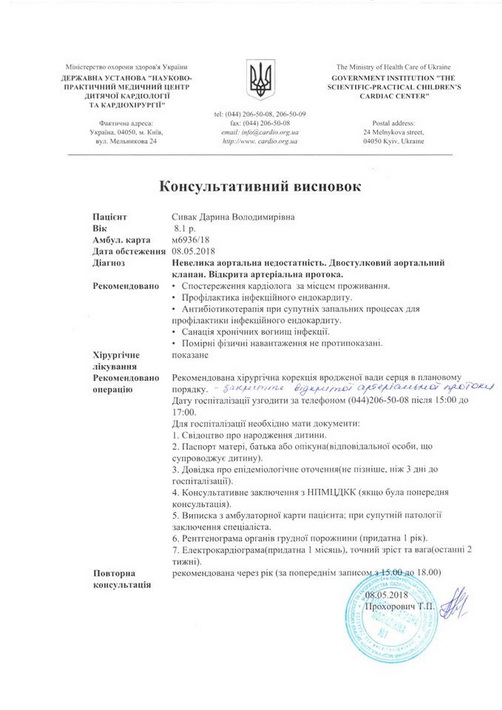

Останнім часом дитина почала швидко втомлюватись, скаржитись на погане самопочуття. Нещодавно при обстеженні було виявлено, що вона має дві вроджені вади серця, про які батьки раніше навіть не здогадувались: відкрита артеріальна протока та двостулковий аортальний клапан.

“Нещодавно ми були на консультації в двох київських кардіологічних центрах – в Науково-практичному медичному центрі дитячої кардіології та кардіохірургії та в Національному інституті серцево-судинної хірургії ім. М.М. Амосова. Кардіохірурги рекомендують якнайшвидше провести операцію із закриття артеріальної протоки. Вартість самого окклюдера складає близько 80 000 грн (без врахування інших витрат). Коштів на придбання окклюдера, а в подальшому – штучного аортального клапана для проведення операцій ми не маємо. Дуже сподіваємось на допомогу небайдужих людей. Будь ласка, врятуйте сердечко нашої донечки!”, – звертається до всіх небайдужих Анна.